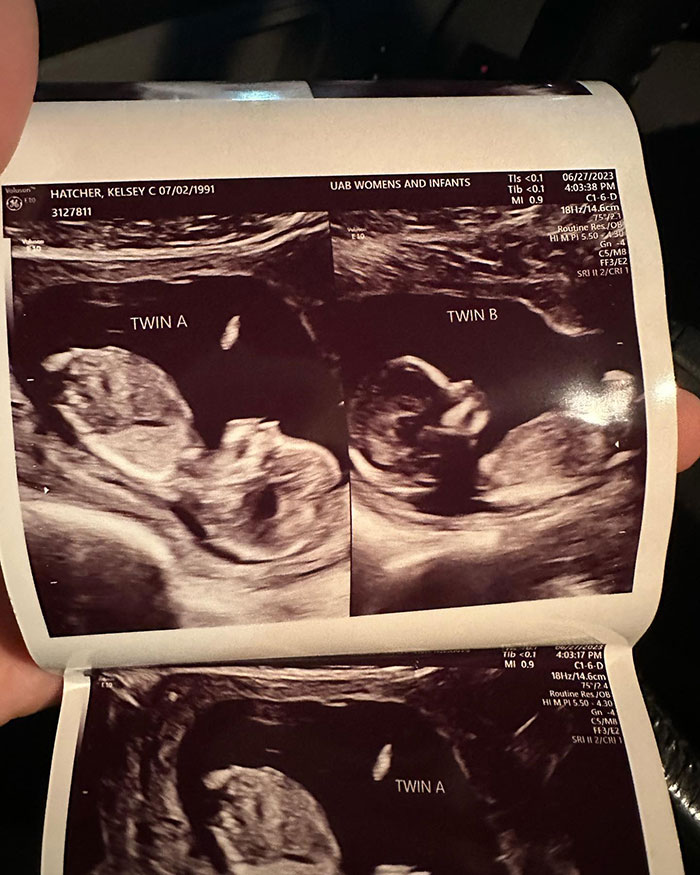

Kelsey Hatcher has a rare condition where she lives with a double uterus, expecting a child in each of the organs.

The expecting mom from Alabama, USA, was in fact born with two functional uteri that each have their own cervix.

Kelsey Hatcher is expecting two girls, pregnant in two sets of uterus, a rare condition she was born with

Upon discovering her pregnancy last spring, followed by a first ultrasound, Kelsey shared the amazing news that she was not only pregnant but expecting babies in both organs, with her husband Caleb.

The anticipated girls are reportedly developing normally, with the most difficult factor of Kelsey’s pregnancies being centered around the timing of the births, which could happen at the same time or separately.

As a result of the girls each growing in their own uterus with their own placenta, the specialists still speculate whether the babies will be twins or siblings.